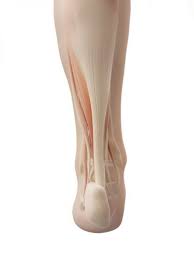

D'un point de vue biomécanique, il permet la propulsion lors de la marche et joue le rôle d'amortisseur lors de la. Bone is living tissue and responds to stress esp. Même si le tendon d'achille fait partie des tendons les plus robustes du corps humain, il peut faire l'objet de blessures et d'affections.

Les tendinopathies du tendon d'achille se rencontrent sur 2 sites ;

Les douleurs sont intenses les douleurs sont tellement intense qu'elles peuvent imposer la prise de morphine et faire. Je fais de la course à pied. Le tendon d'achille est souvent désigné comme étant le tendon le plus long, fort et épais de tout le corps humain (bianchi et martinoli, 2007):